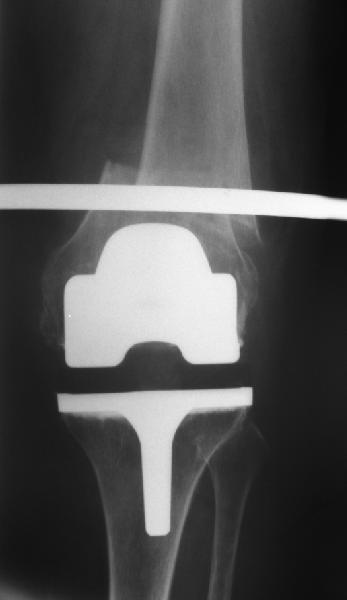

Оперирована по поводу перипротезного перелома н/з бедренной кости Оперирована по поводу перипротезного перелома н/з бедренной кости в ноябре 2010г.Диагноз:закрытый оскольчатый перелом бедренной кости в н/3 со смещением отломков, состояний после эндопротезирования коленного сустава от 2009г.Операция:артропластика коленного сустава, остеосинтез бедренной кости пластиной с угловой стабильностью.В июле операция по поводу несросшегося перелома н/3 бедренной кости,перелом пластины:взятие костного аутотрансплантата из гребня подвздошной кости, удаление пластины, костная аутопластика, остеосинтез бедренной кости пластиной с угловой стабильностью.На контрольном снимке от октября 2012г.- несросшийся перелом бедренной кости, ложный сустав.Что еще можно предпринять? Существуют ли методы лечения, кроме операционных? Поможет ли в данном случае гравитационная терапия7 Или ждать когда все-таки произойдет сращение или еще раз сломается пластина?И произойдет ли сращение вообще? Помогите советом.

Надо удалять пластину и либо вновь синтезировать пластиной, либо делать остеосинтез внутрикостным стержнем. Мы предпочли бы второй вариант. Стержень лучше вводить сверху. Запереть получается очень надежно. В отличие от пластины. стержень можно динамизировать, то есть за счет введения винта вверху в овальное отверстие можно оставить возможность для сближения фрагментов.

Добрый день. Оперировать не рекомендовали. После 3-х лет после операции- вот такая картина. Прокомментируйте пожалуйста снимки.

Снимок только в одной проекции, для более полной оценки ситуации надо и фас увидеть. И в первую очередь узнать о клиническом статусе - жалобы, ось, длина, амплитуда движений в колене, опоросопособность, потребность в дополнительной опоре?

В предыдущем сообщении к сожалению не удалось прикрепипь все снимки.Сейчас это исправляю.Высылаю все снимки в хронологии.

Жалобы следующие:

1.дискомфорт в области крепления пластины ( нужно найти определенное положение, иначе ощущается боль), 2.укорочения конечности в общем не ощущается,

3.колено в суставе полностью не сгибается, но котрактура была еще и до операции по эндопротезированию сустава, сгибалось только на 90 град. После перелома сгибается еще меньше.( Ну это уже не самая большая проблема по сравнению с несрастанием),

4.Хожу с дополнительной опорой на трость, полной нагрузки не даю, т.к. опасаюсь повторного перелома пластины.

По-поводу "оперировать не рекомендовали", имела ввиду своих лечащих врачей, говорили, что гарантии никакой дать не могут на сращение перелома."Ходишь и ходи" Будут проблемы - будем дальше думать.

Прошу Вас прокомментировать динамику. Почему пластина опустилась? И наблюдается ли все-таки сращение?